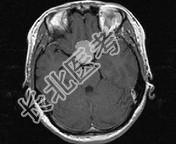

单项选择题女,32岁, 右眼视物模糊1年,加重2月, 请根据所提供图像,选择最可能的诊断是 ( )

A、鞍区转移瘤

B、鞍区海绵状血管瘤

C、鞍区动脉瘤

D、鞍区垂体瘤

E、鞍区脑膜瘤